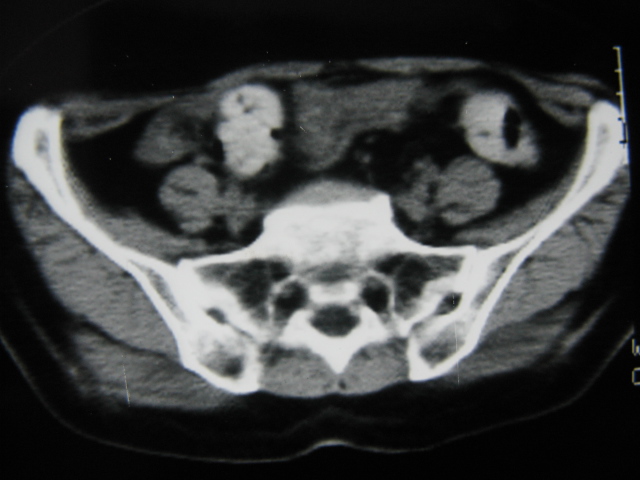

患者,女,64岁,2002年诊断为宫颈癌,当时只做过放,化疗。现在诊断:(1)宫颈癌。(2)直肠癌。请同道们讨论,探讨。另外肠壁为啥密度这么高,ct值约112hu。患者没有做过增强和造影。

高密度的不是肠管影,是肠管内的粪便影

患者直肠病变,排便不畅,粪便硬结造成,更高密度如钡灌肠者都可出现

难定宫径癌,直肠癌

我也碰到过几例,最离奇的一例是全结肠呈造影样高密度,患者直肠癌(首次发现),以往没有吃药,只有约半年时间长的胃纳差,排便不畅(据患者说每次大便只能拉出少许黄水)

不一定有意义,可清洁灌肠后复查